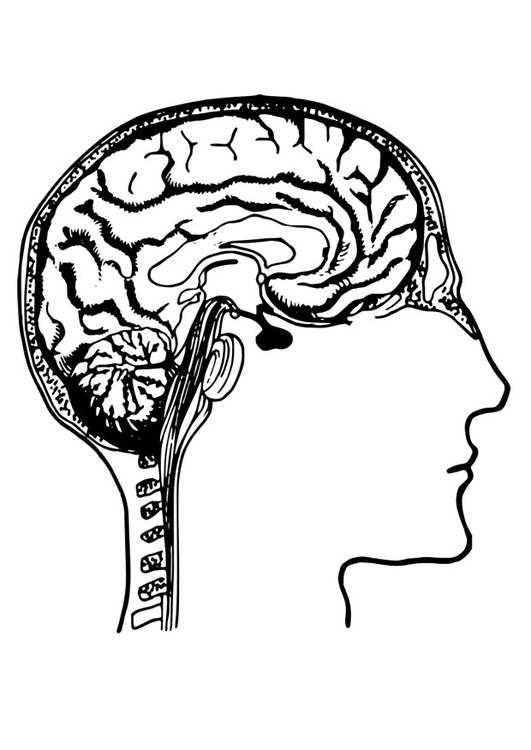

Source: coloringhome.com

Source: coloringhome.com